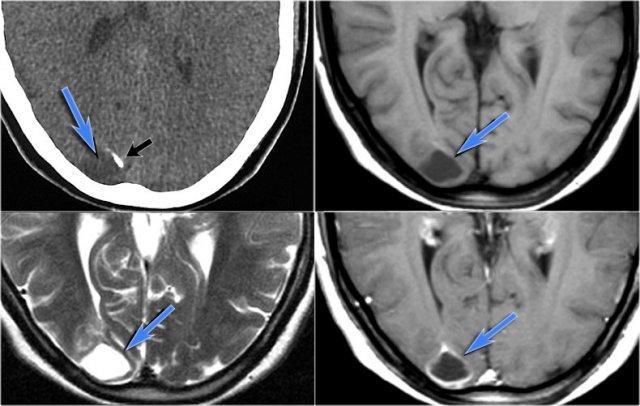

Cavernoma bao gồm các tiểu thùy có kích thước khác nhau chứa các sản phẩm máu ở nhiều giai đoạn tiến triển khác nhau, tạo nên hình ảnh đặc trưng “bỏng ngô” (popcorn).

Một vành hemosiderin hoàn chỉnh bao quanh tổn thương, ngoại trừ trường hợp có chảy máu gần đây.

CT không tiêm thuốc cản quang có thể cho thấy một nốt tăng tỷ trọng hoặc vôi hóa, nhưng trong 50% trường hợp, cavernoma sẽ không được phát hiện trên CT.

Chuỗi xung T2W và T2* gradient echo cho thấy nhiều cavernoma.

Lưu ý hình ảnh “bỏng ngô” với vành hemosiderin ngoại vi trên chuỗi xung T2W.

Các tổn thương gần như hoàn toàn màu đen trên chuỗi xung gradient echo do xảo ảnh blooming.

Chuỗi xung T2* và hình ảnh trọng số độ nhạy từ (SWI) làm tăng đáng kể độ nhạy của MRI trong việc phát hiện các cavernoma nhỏ.

Năm chấm đen ở bán cầu đại não trái trên chuỗi xung T2* cũng là cavernoma và không thể nhìn thấy trên chuỗi xung T2W.

CT không tiêm thuốc cản quang cho thấy một vôi hóa nhỏ ở nhân thấu kính bên phải.

CT có tiêm thuốc cản quang cho thấy một dị dạng tĩnh mạch dẫn lưu cavernoma vào tĩnh mạch não trong bên phải.

Chuỗi xung T2W mặt phẳng coronal cho thấy dị dạng tĩnh mạch dưới dạng một khoảng trống dòng chảy hình đường cong.

Cavernoma ở hồi sau trung tâm trên chuỗi xung T1W, T2W và SWI.

Lưu ý hình ảnh “bỏng ngô” và xảo ảnh blooming.